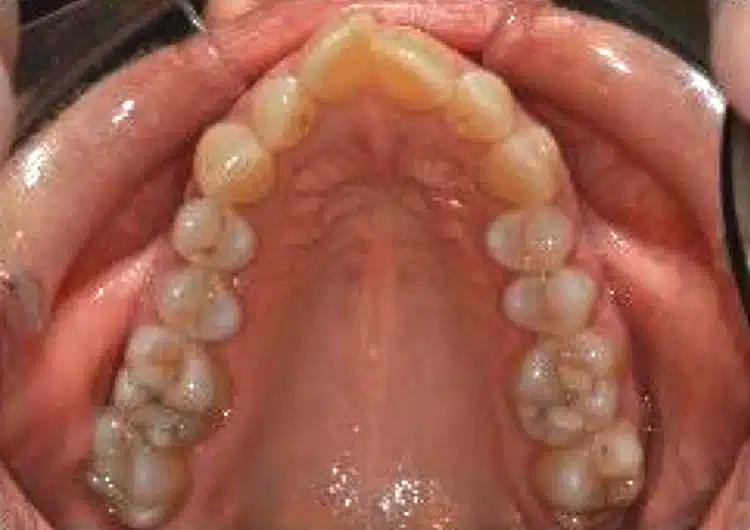

Before surgically assisted osteogenic orthodontic treatment